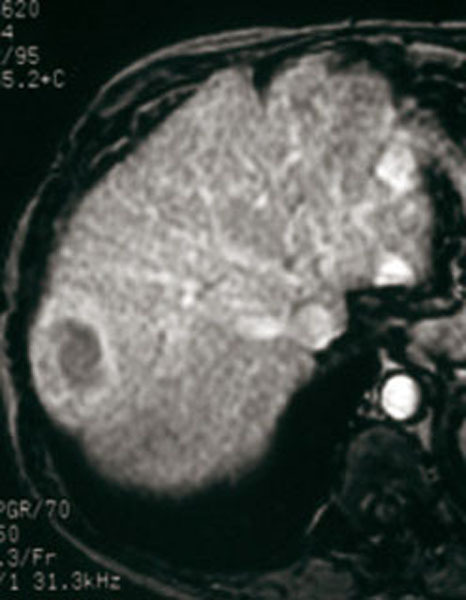

Aspect caractéristique IRM triphasique (sans injection, temps artériel = tumeur hypervasculaire, temps portal - wash out).